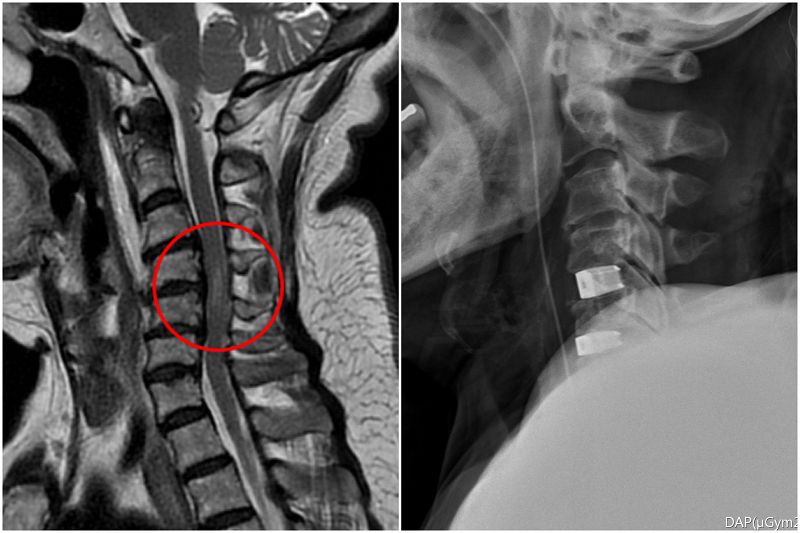

李建輝主任表示,當時在急診看到婦人,除主述四肢癱軟無力,發現她一直在用腹式呼吸,無法自然呼吸,令他警覺有可能是頸椎神經受損,因為控制橫膈的神經就在頸椎附近,透過檢查果然是第四到六節的神經被壓迫,且能清楚看到她的骨刺壓迫已造成脊髓損傷,有癱瘓風險,須儘快手術清除和重建,提高恢復的可能性,隨即在隔天進行手術,清除突出的椎間盤後放入填充物,並用支架固定頸椎。